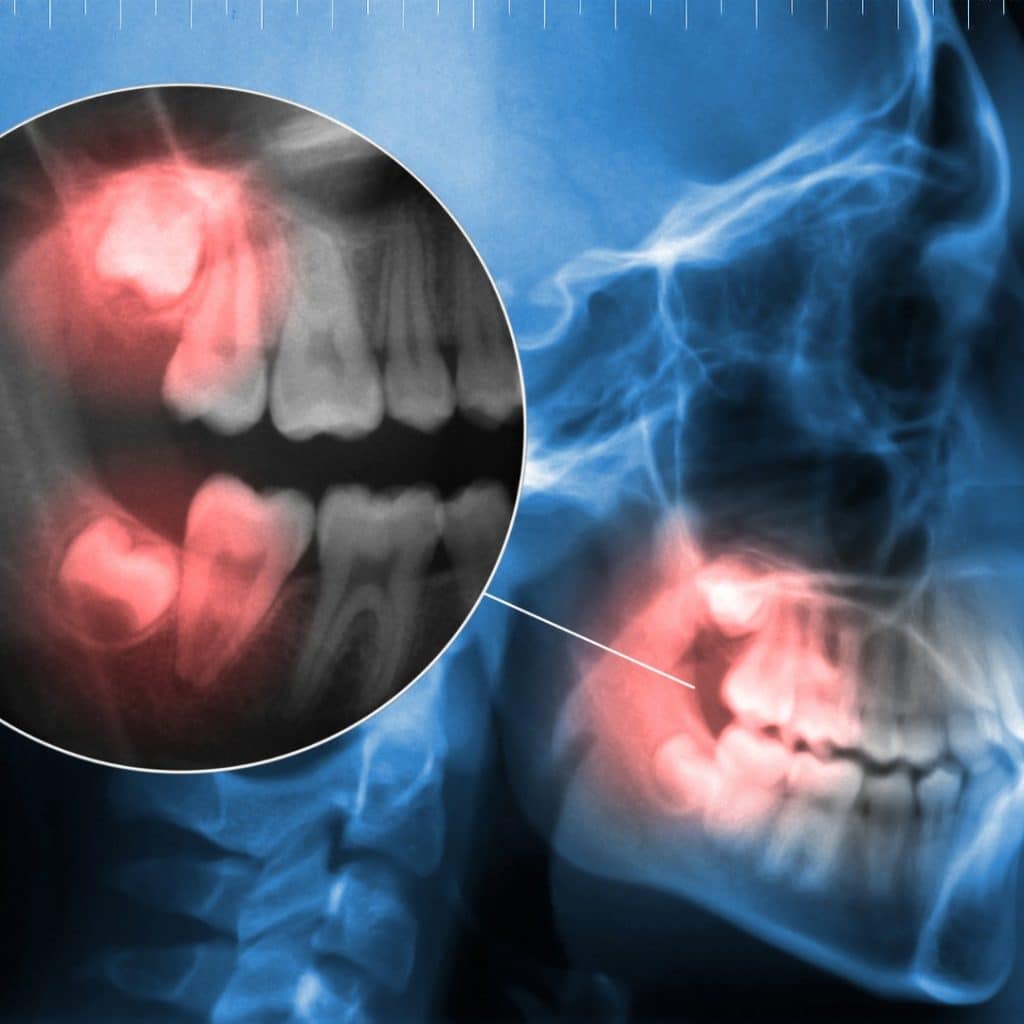

Røntgenbilde av kjeve som viser visdomstann med betennelse, markert med rødt. Digital tannrøntgen med fokus på tannproblemer som impaktert visdomstann.

Enten det gjelder tannverk, infeksjon, betennelse i visdomstann, knekt tann eller hevelse, gjør vi vårt beste for at du skal føle deg bedre så raskt som mulig – og trygt ivaretatt hele veien.